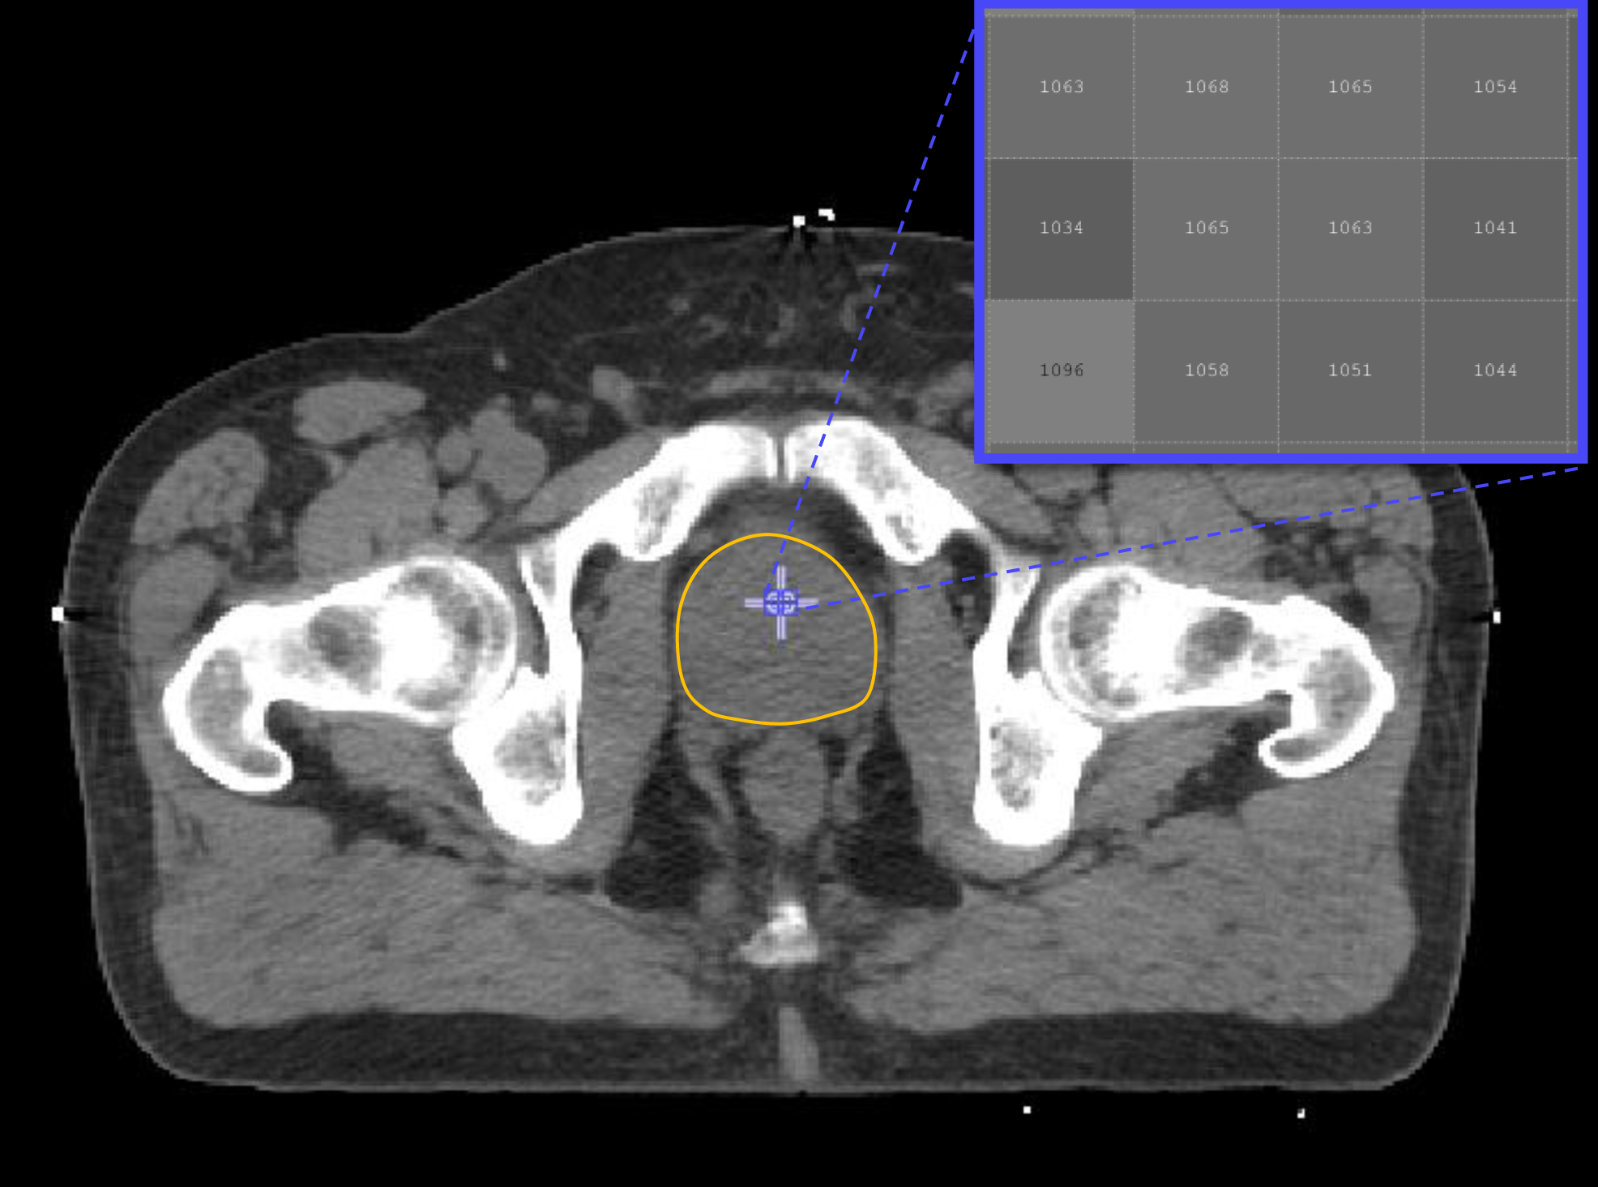

Joe O’Sullivan, Professor of Radiation Oncology at The Patrick G Johnson Centre for Cancer Researchat Queen’s University Belfast, Co-Director of the Movember Centre of Excellence and Clinical Director of Oncology in Belfast Trust explains: “We have made huge progress in personalised treatment for prostate cancer patients through the development of new tests to identify the type of tumour, as well as gaining a deeper understanding of the role of radiotherapy in prostate cancer therapy.”

“Through these new tests, we can potentially identify patients with particularly high risk prostate cancer to determine what treatment will be most effective, tailored to the particular tumour.